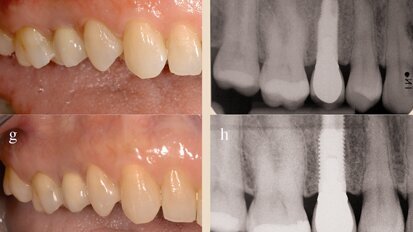

Neoss photos

Neoss Implantat System